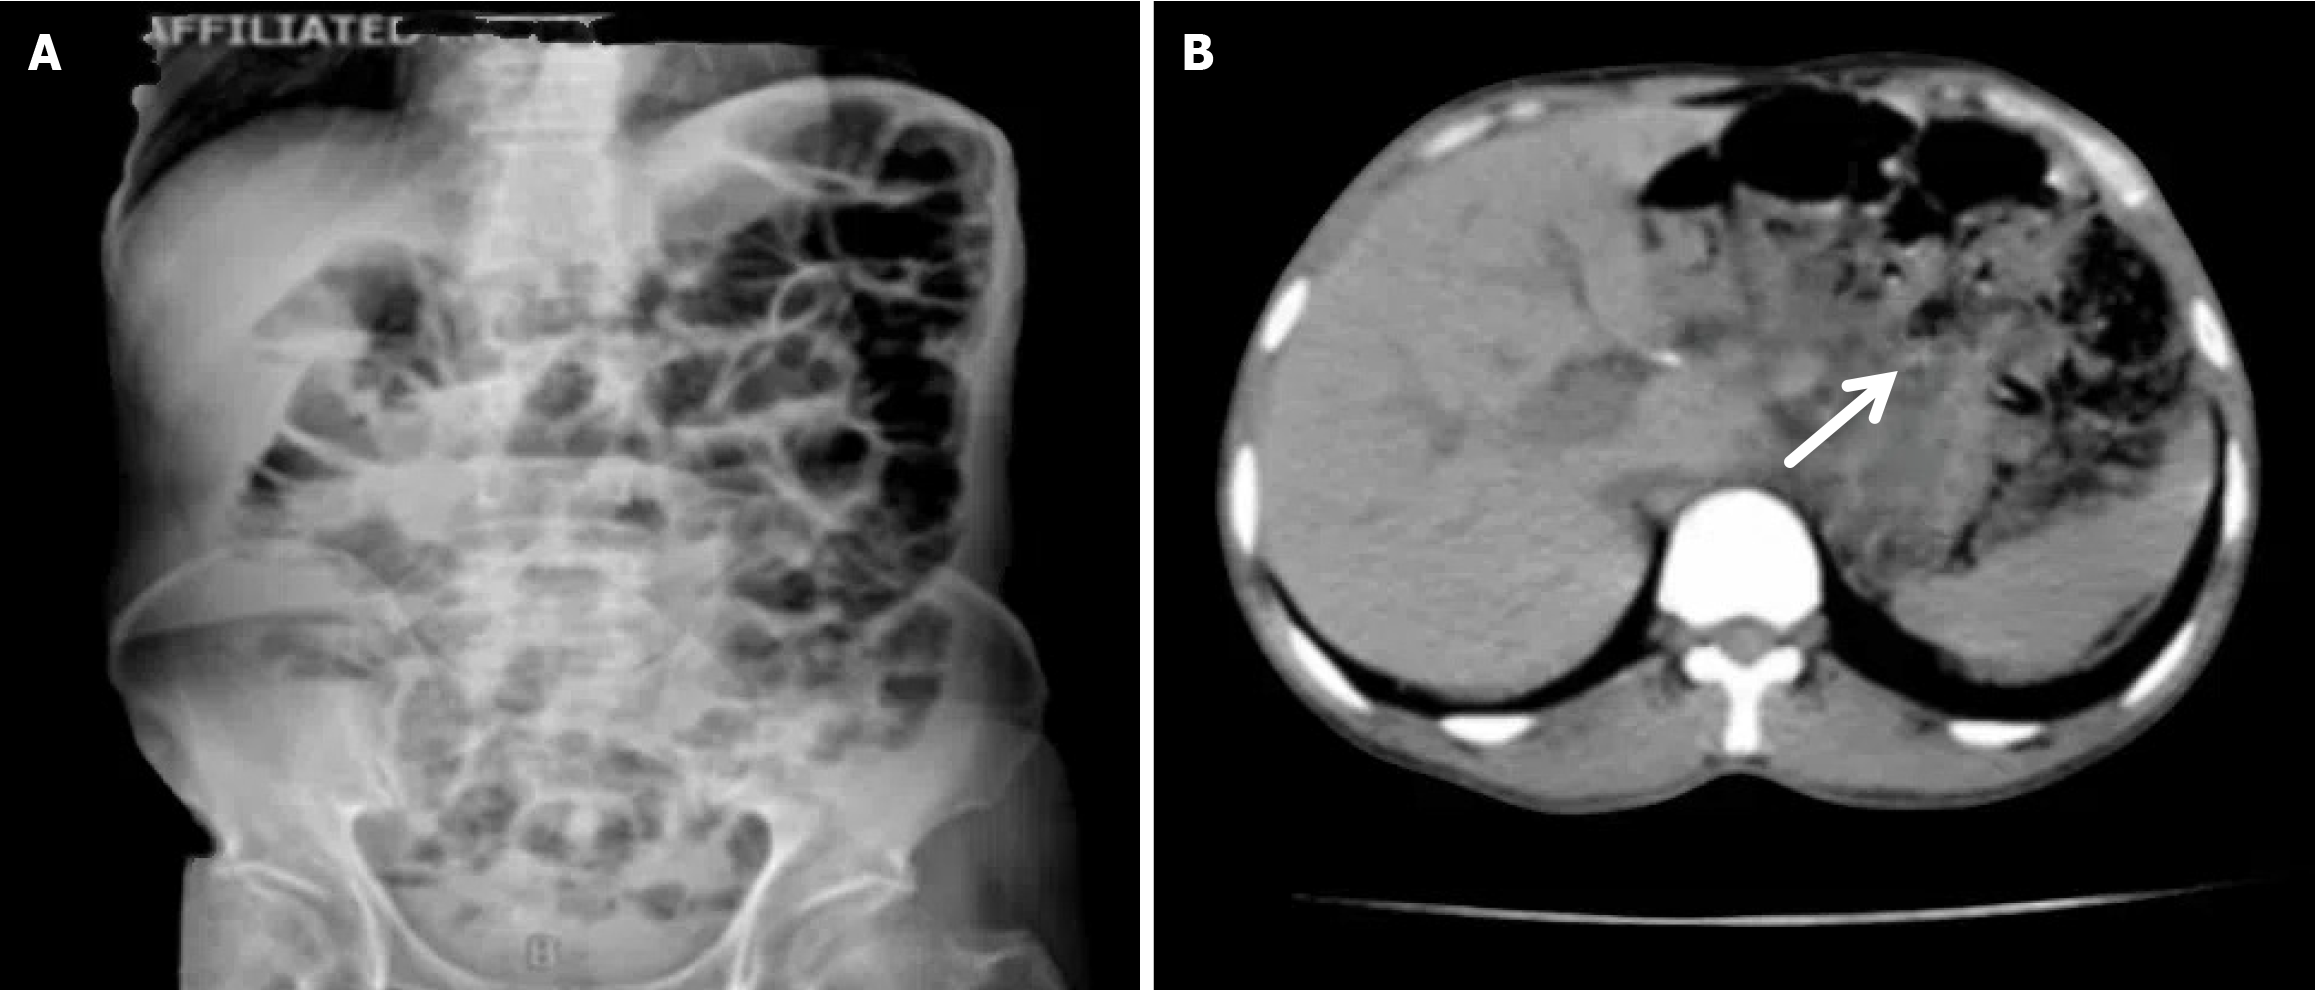

Compared with the modified group, the Orr group had a greater incidence of anastomotic leakage (AL) and short-term complications of anastomotic ischemia, although there was no significant difference between the two groups. Furthermore, Fisher’s exact probability analysis revealed that the incidence of reflux esophagitis, anastomotic ulcers by endoscopic examination, and intestinal obstruction in the Orr group was greater than that in the modified group at the 6-month postoperative follow-up period (P < 0.05) (Tables 3, 4 and 5).

There was no significant difference in weight loss between the two groups at 1 month after the operation (P > 0.05). However, in the improved group, the weight of the improved group was less than that of the original group at 3 months and 6 months after the operation (P < 0.05). The hemoglobin in the Orr group decreased significantly at 1 and 3 months after the operation compared with that in the improved group (P < 0.05), but there was no significant difference between the two groups at 6 months after the operation (P > 0.05). There was no significant difference in total protein or serum albumin between the two groups at 1 month, 3 months, and 6 months after the operation (P > 0.05) (Figures 2, 3, 4, 5 and 6, Table 6).

Our results showed that the modified Roux-en-Y group was better than the traditional Roux-en-Y group in terms of perioperative indicators, postoperative complications, and quality of life. As shown in Table 1, the digestive tract reconstruction time (21.46 ± 2.77 minutes) and operation time (160.9 ± 9.44 minutes) in the modified group were significantly shorter than those in the original group (62.25 ± 7.79 minutes and 211.7 ± 19.66 minutes, respectively) (P < 0.05). In addition, the amount of intraoperative bleeding in the improved group was significantly lower than that in the original group (P < 0.05). The reason may be the complexity and greater number of procedures, and the mesenteric vessels of the jejunum also need to be disconnected in the Orr group, whereas in the improved group, only one window needs to be opened in the jejunum to complete all gastrointestinal reconstruction.

The nutritional parameters are likely affected by the progression of cancer or a patient’s performance status. During the follow-up periods of 1 month, 3 months, and 6 months after the operation, the weights of the two groups decreased significantly at 1 month after the operation, but there was no significant difference between the two groups. However, the weight loss of the improved group decreased less than that of the Orr group at 3 months and 6 months after the operation (P < 0.05). The hemoglobin level of the Orr group decreased significantly compared with that of the modified group at 1 month and 3 months after the operation (P < 0.05), but there was no significant difference between the two groups at 6 months after the operation (P > 0.05). Our results revealed that patients in the improved group had better nutritional status than those in the earlier group did, which may be related to more recent complications and poorer postoperative status in the former group; however, the underlying mechanism must be further explored. Research conducted by Yang et al[27] explored the impact of different gastrointestinal reconstruction methods on postoperative intestinal microbiota composition and diversity and nutrient absorption. This study highlighted the need to consider alterations to the gastrointestinal microflora when selecting a reconstruction approach for GC surgery. The authors also emphasized the need for further metabolomics analyses to elucidate these effects in the context of GC surgery.